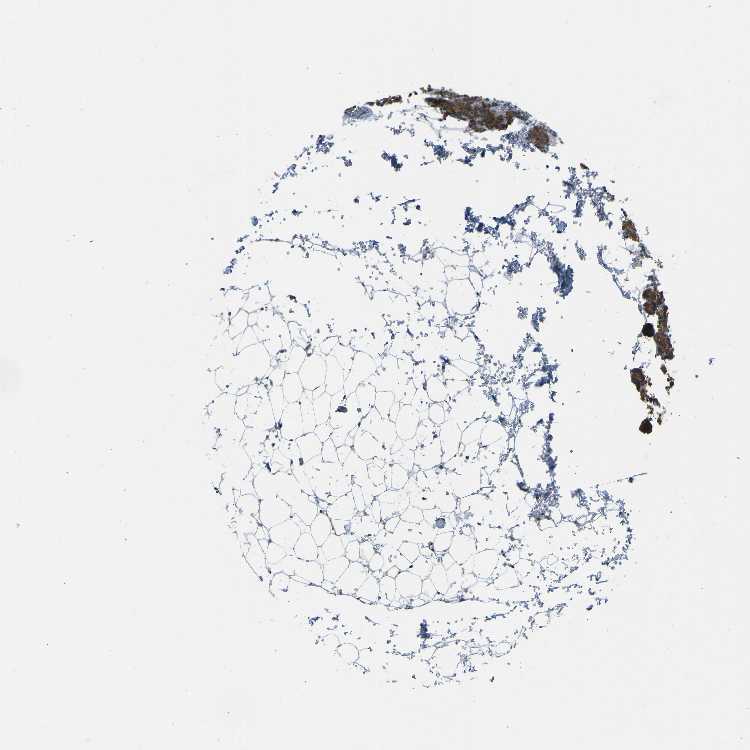

TISSUE PRIMARY DATA PARATHYROID GLAND Show tissue menu

PARATHYROID GLAND - Antibody stainingi

Antibody staining in the annotated cell types in the current human tissue is reported as not detected, low, medium, or high, based on conventional immunohistochemistry profiling in selected tissues. This score is based on the combination of the staining intensity and fraction of stained cells.

Each image is clickable and will lead to virtual microscopy that enables deeper exploration of all samples and also displays staining intensity scores, fraction scores and subcellular localization as well as patient and tissue information for each sample.

Antibody HPA019155Antibody HPA075293Antibody CAB020836

Glandular cells HighHighMedium